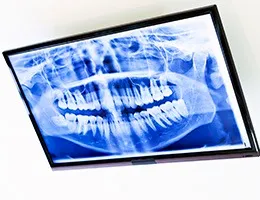

Digital X-Rays

Traditional dental X-rays required a lot of time to develop and exposed people to uncomfortable amounts of radiation, but thanks to the advent of digital dentistry, these problems have both been solved. Digital X-rays can create crystal-clear images almost instantly, and they emit up to 80% less radiation as well. Plus, the images can be easily blown up, rotated, and color-coded so you can easily go over them with your dentist.